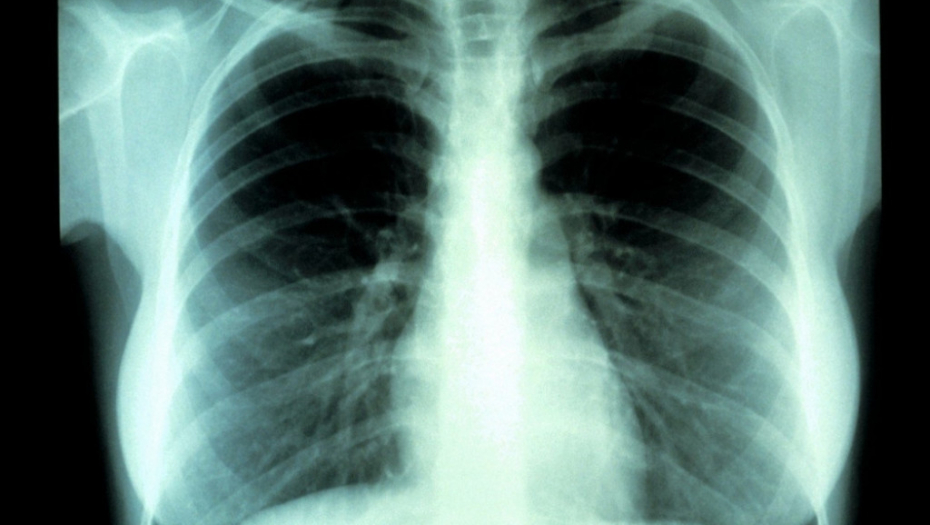

Hronična opstruktivna bolest pluća (HOB) karakteriše se ograničenjem protoka vazduha u disajnim putevima. Često je ograničenje protoka vazduha progresivno i udruženo sa zapaljenskom reakcijom pluća na štetne čestice ili gasove.

Reč "hronična" znači da se bolest ne povlači, a "opstruktivna" da je delimično blokiran protok vazduha u disajnim putevima.

Od HOB-a najčešće obolevaju pušači ili bivši pušači, kao i osobe koje žive u kućama sa mnogo gasova. Prvi simptomi su kašalj i iskašljavanje sluzavog ili "prljavog" ispljuvka, otežano disanje, gušenje pri fizičkom naporu, ali i duži oporavak posle prehlade.